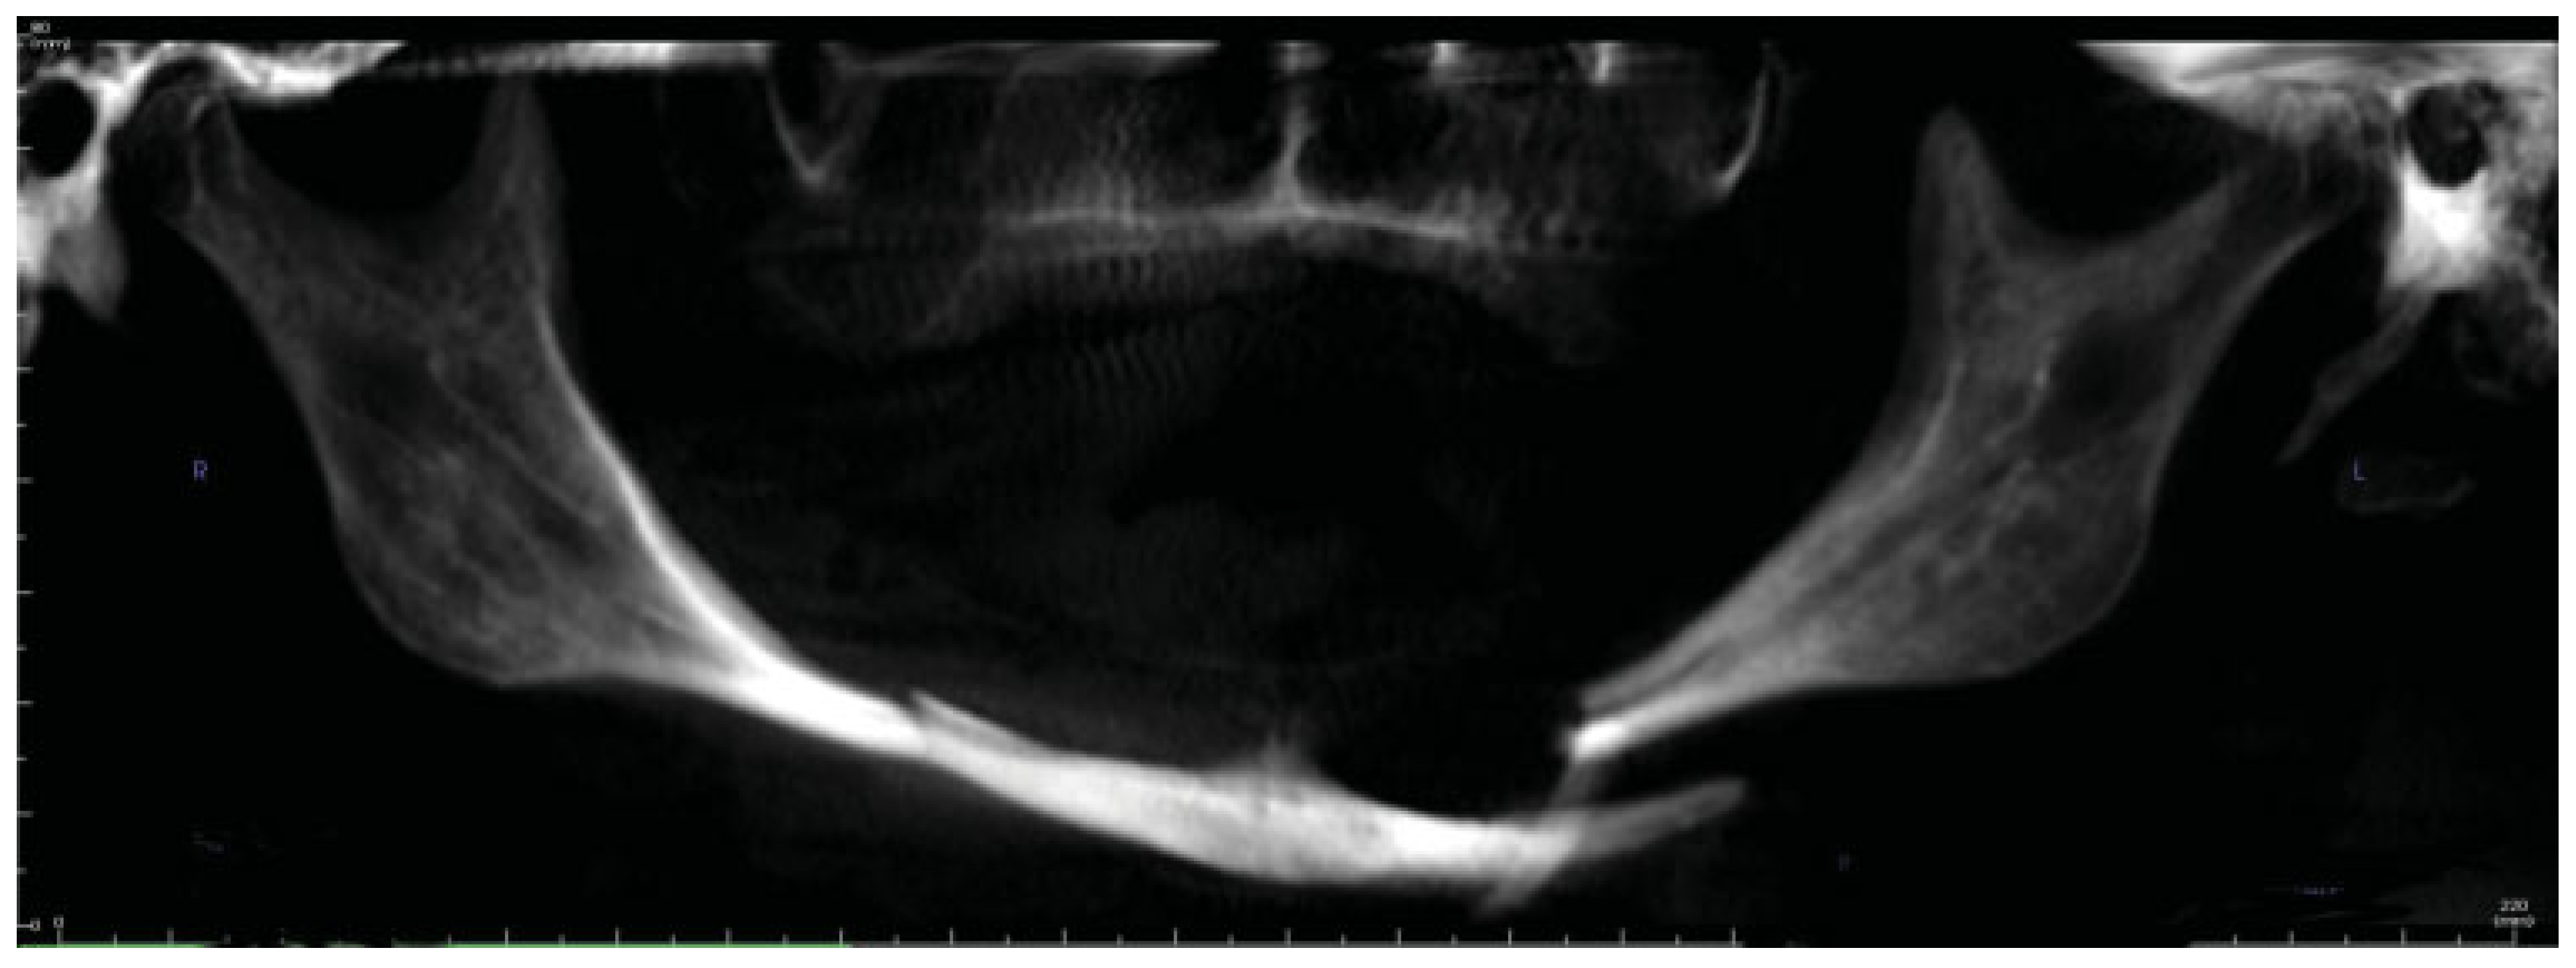

A 69-year-old woman had a fall 1 week prior to presentation while walking with her dog. She experienced worsening face and jaw pain and eventually presented to her primary medical doctor who ordered plain films and diagnosed her with a mandible fracture. She then self-referred herself to the authors for evaluation. Her past medical history was significant for chronic obstructive pulmonary disorder, hypothyroidism, hypercholesterolemia, anxiety, and depression. She stated that she recently quit smoking. Her dental history was significant for extraction of all upper and all lower teeth when she was in her 20s. On examination, she had moderate bruising of her neck bilaterally and submental area. Her intraoral mucosa was intact. A cone beam computed tomography (CBCT) was performed which showed bilateral mandibular body fractures as well as severe atrophy of the mandible, with the height of the mandible less than 4 mm at the fracture sites (Figure 1). Utilizing the DICOM data from the CBCT VSP was used utilizing Depuy Synthes/Materialise PROPLAN CMF. A 3-d image of the fractured mandible was constructed and the fracture was virtually reduced (Figure 2 and Figure 3). Stereolithographic models of the fractured and reduced mandible were fabricated and a bending template was adapted over the reduced mandible model and a 2.5 reconstruction plate was subsequently bent according to the template/model (Figure 4).

Figure 1. Cone beam computed tomography reconstruction showing atrophic mandible with bilateral body fractures.